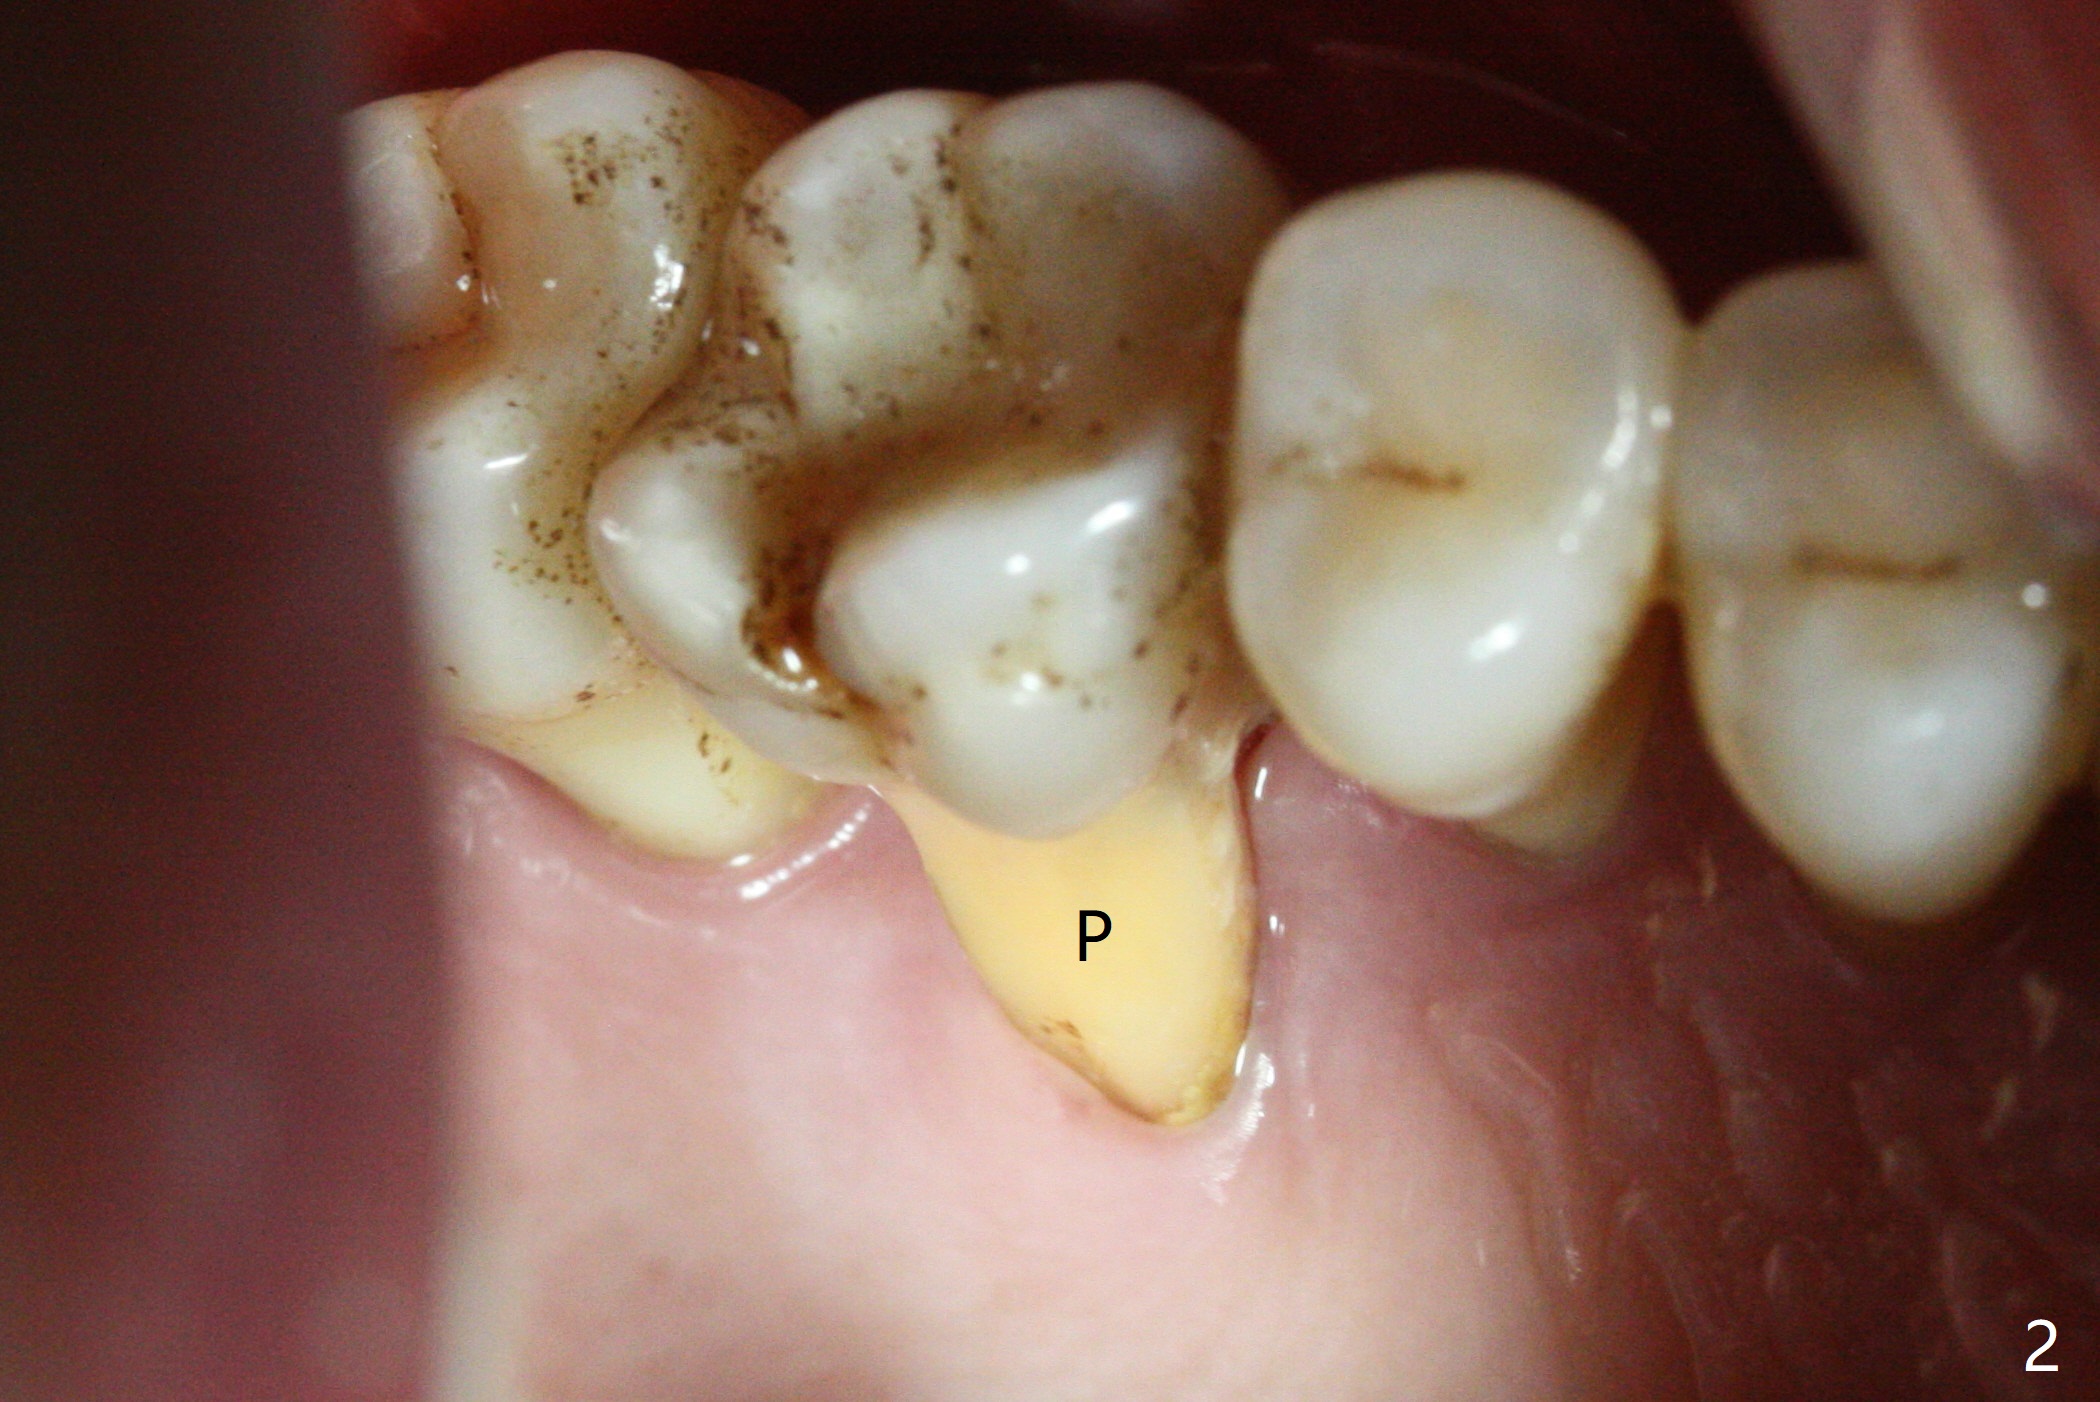

The tooth #3 has gingival recession moderate buccally (Fig.1) and severe palatally (Fig.2 P). The remaining bone height is estimated 4 mm (Fig.3). After extraction and debridement, the 3 sockets are packed with 2% Lidocaine 1:50,000 Epinephrine saturated gauze (Fig.4). When the gauze is removed from the buccal sockets (Fig.5 black area), the buccal portion (B) of the septal gingiva (*) is sectioned from the buccal gingiva (Fig.6 curved white line) and elevated from the underlying septal bone and pushed palatally (arrow). The septal gingiva (including the buccal portion) will be the palatal soft tissue wall of the subsequent osteotomy, providing blood supply to allograft to be placed. In short, the septum (through the buccal socket) will be the osteotomy site.